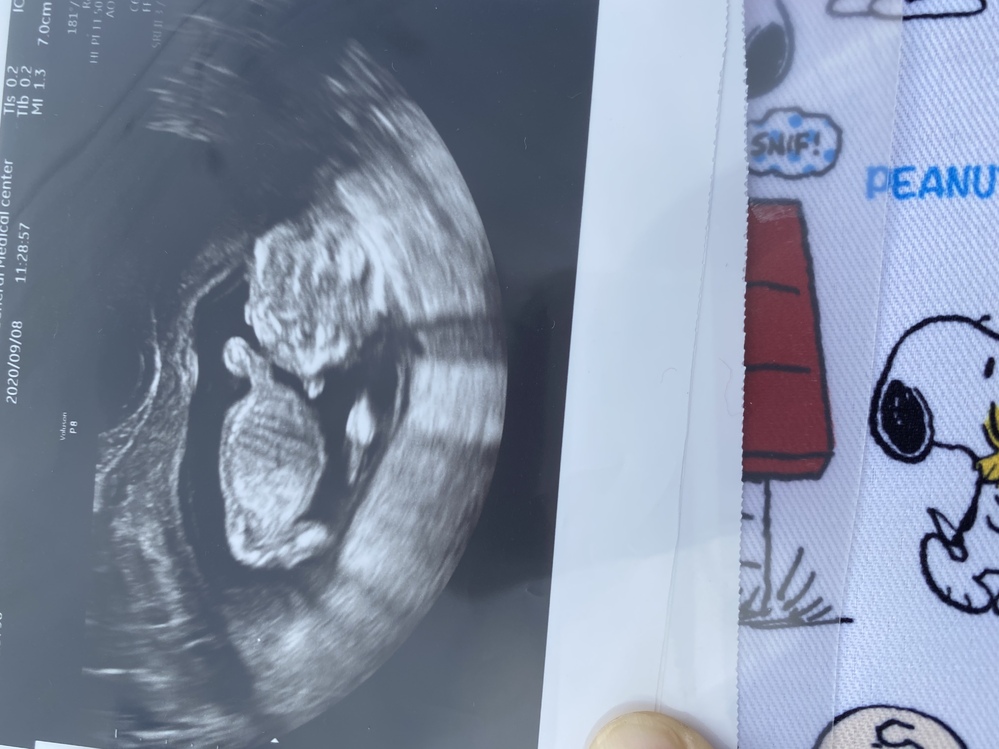

エコー写真 性別の見分け方 男の子女の子別エコー 妊娠週まとめてみました ママびよりウェブ

医療監修 エコー写真を妊娠の経過別に紹介 写真の見方や性別の見分け方 ママリ

エコー写真を妊娠の経過別に紹介 見方や性別の見分け方